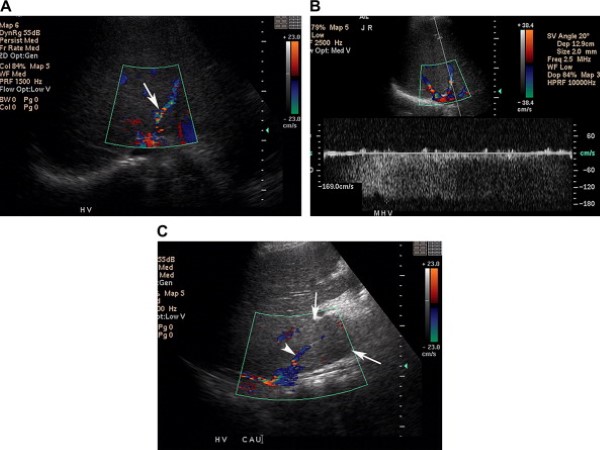

Đảo chiều dòng chảy trong tĩnh mạch cửa và các nhánh của nó, từ dòng chảy về gan sang dòng chảy ngược, là một dấu hiệu đặc trưng của tăng áp lực tĩnh mạch cửa và thường xuất hiện ở các bệnh nhân có bệnh gan tiến triển. Một manh mối để chẩn đoán đảo ngược dòng chảy này là dấu hiệu xác định ở rốn gan, động mạch gan và tĩnh mạch cửa có dòng chảy ngược chiều nhau (Hình 15) (xơ gan, Child-Pugh độ C) [4].

Hình 15. Đảo chiều dòng chảy trong tĩnh mạch cửa ở bệnh nhân nam 45 tuổi có tiền sử tăng áp lực tĩnh mạch cửa do xơ gan, nghiện rượu. (Hình A) Ảnh siêu âm màu chứng minh dòng chảy bên trong tĩnh mạch cửa chảy đi xa đầu dò (màu xanh)(mũi tên). Lưu ý dòng chảy hướng tới đầu dò ở động mạch gan (đầu mũi tên). (Hình B) Ảnh Doppler xác định đảo ngược dòng chảy khi thấy sóng nằm bên dưới đường cơ bản của thang Doppler.

Đối với các bệnh nhân xơ gan hoặc nghi ngờ có u gan ác tính, việc phân biệt giữa huyết khối đơn thuần và huyết khối ác tính là bắt buộc. Chứng minh dòng chảy lìa gan có nhịp động mạch bên trong huyết khối của tĩnh mạch cửa có độ nhậy vừa phải (62%) nhưng độ đặc hiệu cao (95%) trong chẩn đoán huyết khối ác tính tĩnh mạch cửa (Hình 17) [7,8]. Phân biệt huyết khối lành tính với huyết khối ác tính là chủ chốt để tiên lượng bệnh và chọn bệnh nhân cho phẫu thuật. Nếu cần thiết, người ta có thể chọc hút kim nhỏ huyết khối tĩnh mạch cửa dưới hướng dẫn siêu âm để thiết lập chẩn đoán [9].

Hình 17. Huyết khối ác tính tĩnh mạch cửa ở bệnh nhân nam 72 tuổi có tiền sử ung thư biểu mô tế bào gan. Chọc hút kim nhỏ huyết khối tĩnh mạch cửa xác định huyết khối là ung thư biểu mô tế bào gan. (Hình A) Ảnh siêu âm thang xám ở rốn gan phát hiện tổ chức giảm âm lấp đầy và gây giãn lòng tĩnh mạch cửa và các nhánh của nó (các mũi tên). (Hình B) Ảnh siêu âm Doppler và màu chứng minh tình trạng có mạch máu bên trong huyết khối. Dạng sóng động mạch sức cản thấp gợi ý huyết khối ác tính do u. (Hình C) Ảnh cộng hưởng từ tiêm thuốc đối quang, thì động mạch cho thấy ngấm thuốc ngoằn ngoèo ở trong huyết khối tĩnh majhc (mũi tên), cho phép xác định huyết khối ác tính. Lưu ý động mạch gan (đầu mũi tên) ngấm thuốc mạnh, hiện rõ.